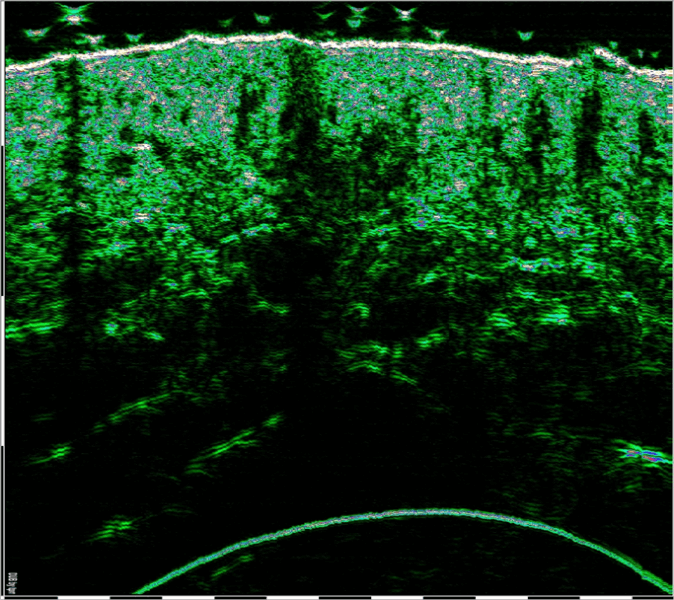

W celu oceny skuteczności terapii z wykorzystaniem fibryny bogatopłytkowej I-PRF oraz S-PRF przeprowadzono badania gęstości akustycznej skóry przed i po podaniu obu frakcji. Zabieg polegał na podaniu fibryny komórkowej i strukturalnej w okolice łuku jarzmowego u pacjentki (62 l.)

Ultrasonografia wysokiej częstotliwości rzędu 75 MHz – HFUS (HIGH FREQUENCY ULTRASOUND) – jest metodą pozwalającą w bezpieczny sposób obrazować wszystkie warstwy skóry. Badanie HFUS pozwala ocenić jej grubość, strukturę wewnętrzną czy zawartość włókien kolagenowych.

Przed zabiegiem u wykonano pomiar gęstości skóry za pomocą głowicy ultrasonograficznej o częstotliwości 75 MH, w miejscach poddanych zabiegowi. Wykonano dokumentację fotograficzną skanów ultrasonograficznych. Na podstawie wykonanych pomiarów dokonano oceny gęstości akustycznej skóry, jako parametru określającego zmianę gęstości tkanki skórnej poddanej terapii.

Pomiar gęstości skóry wykonany przy pomocy DUB SkinScanner , mgr inż. Symon Korzekwa.

Poniższe obrazy ultrasonograficzne: [1], [2], przedstawiają zmianę gęstości akustycznej skóry w obszarze łuku jarzmowego.

Gęstość akustyczna jest to zdolność tkanki do odbicia fali ultradźwiękowej. Jest to skala bezwzględna znormalizowana w zakresie od 0 -255.

Rys. [1] Przed zabiegiem – Gęstość 20 Rys. [2] Po zabiegu – Gęstość 66

W wykonanym obrazowaniu, stwierdzono bardzo charakterystyczny trend wzrostowy gęstości skóry właściwej po podaniu fibryny I-PRF oraz S-PRF. Ten efekt widoczny jest również po drugim zabiegu, czyli po 2 miesiącach terapii.